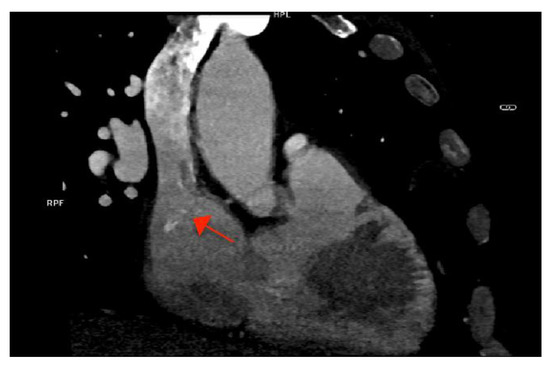

As part of the imaging assessment approach in IE, a thoracic, abdominal, pelvic, and cerebral computed tomography (CT) scan were conducted. The GCFS was visible in the SVC, but there was no evidence of vegetation at this level (Figure 3).

Figure 3. Cardiac computed tomography showing the calcified fibrin sheath in the superior vena cava (arrow), without evidence of vegetations.